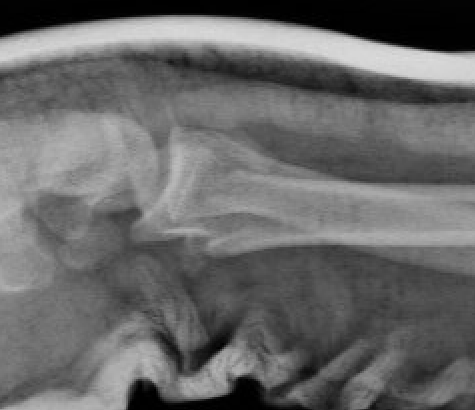

| Volar Barton's fracture | Reverse Barton's fracture | Die Punch |

|

Volar intra-articular fragment Inherently unstable |

Dorsal intra-articular fracture | Depressed articular fragment |

Fracture configurations

| Extra-articular fracture | Intra-articular with scaphoid and lunate fossa fragments | Volar Barton's |

| Dorsal fractures | Volar ulnar fracture | Sigmoid notch involvement |